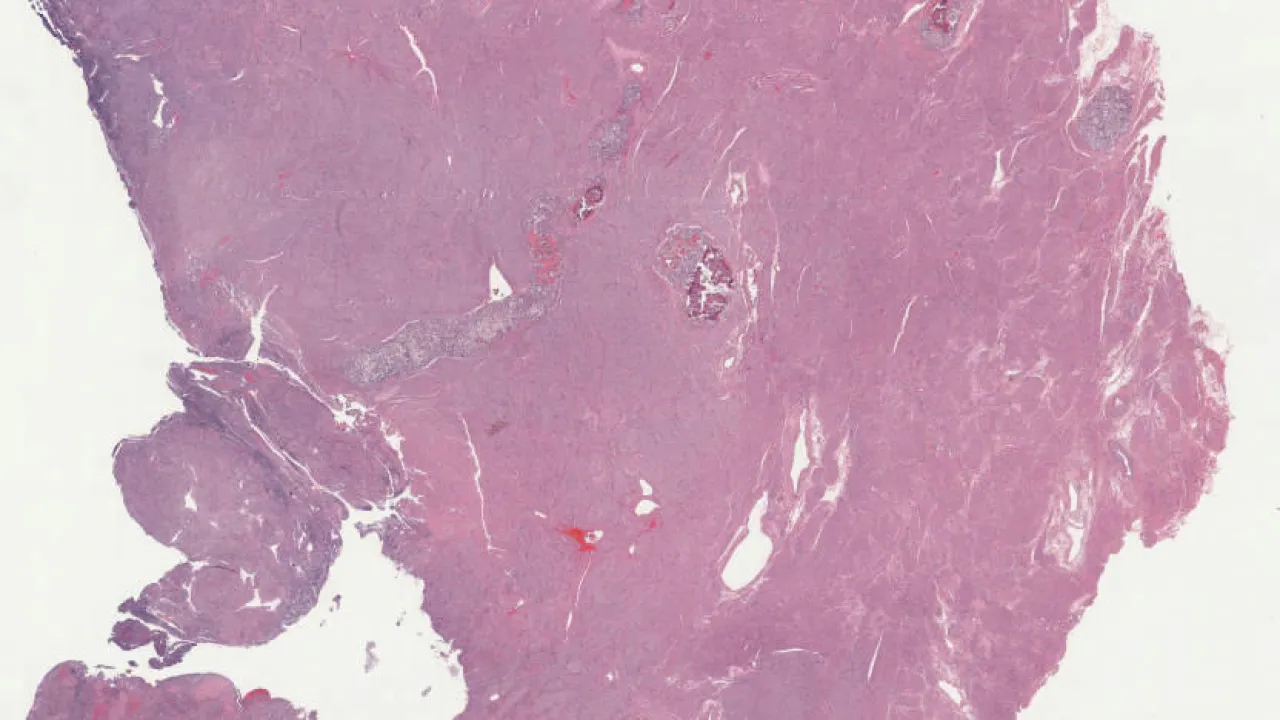

Breast, Ductal carcinoma in situ